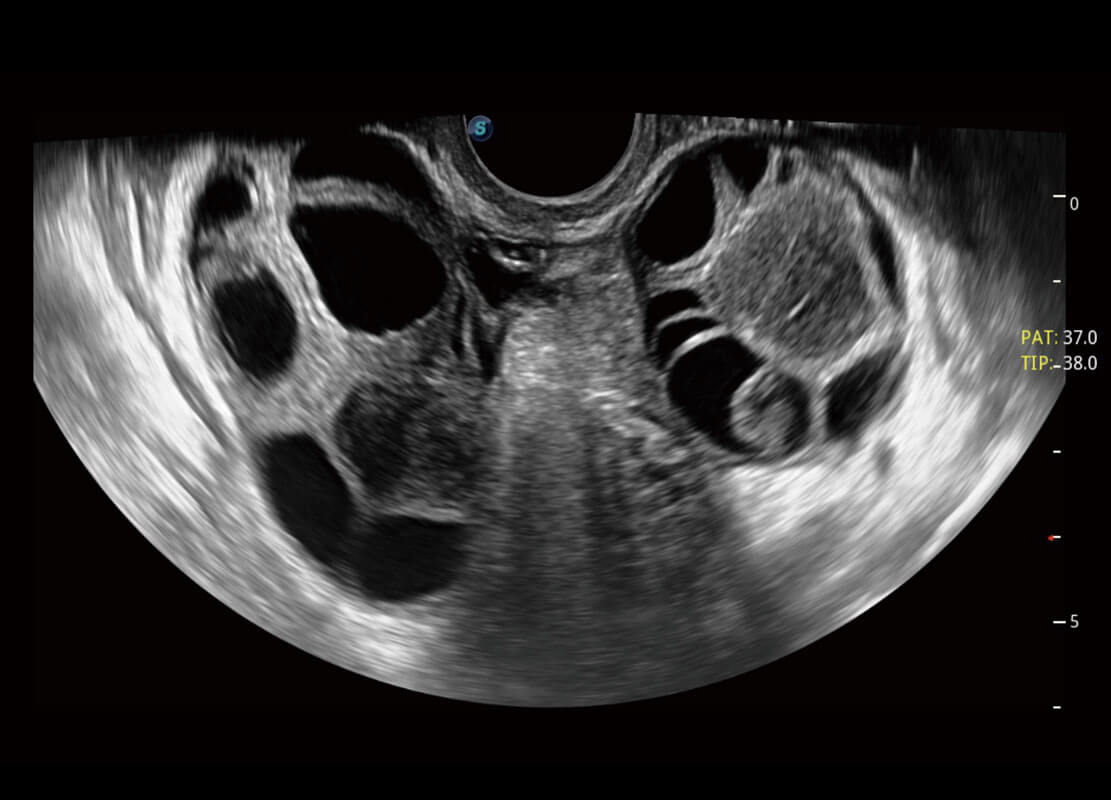

P60優(yōu)異的圖像質(zhì)量搭載??铺筋^,在婦科基礎(chǔ)疾病的診斷、卵泡生長的監(jiān)測、輸卵管通暢情況的判別等方面為您提供生殖應(yīng)用方案。

腔內(nèi)婦科-卵巢